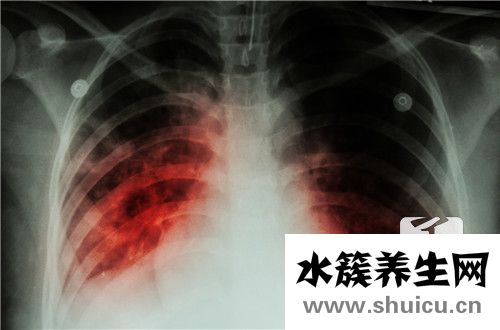

我們平時(shí)接觸的許多疾病都是由炎癥引起的,如婦科炎癥、肺炎、肝炎、腎炎等。炎癥有多種類型,可分為細(xì)菌性炎癥和無菌性炎癥無菌性炎癥主要是物理和化學(xué)因素刺激下的炎癥反應(yīng)。那么,什么是無菌性炎癥?讓我們?cè)敿?xì)看看。

“無菌性炎癥”是人體發(fā)生機(jī)體障礙疾病和頑固疼痛的部位沒有細(xì)菌感染,病理檢查和組織切片找不到任何微生物侵害的跡象,從病理變化上來看是無菌性的,沒有病源菌的炎癥,因而抗生素治療無效。